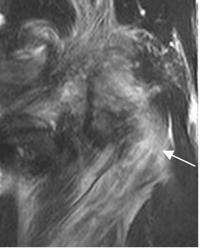

Fig 129. Lesión de la esquina posterolateral

RM coronal en STIR. Edema que compromete el músculo poplíteo, con ruptura de algunas fibras, por lesión GII.